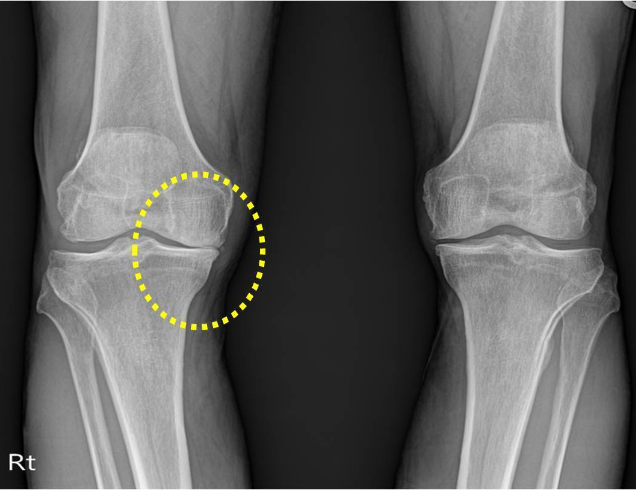

퇴행성관절염

나이가 들면서 자연스럽게 무릎관절의 연골이 변성되고 닳아 없어지는 병입니다.

퇴행성관절염의 증상

- 퇴행성 관절염 초기 서있거나 걸을때처럼 무릎에 체중부하가 클 때 통증이 생깁니다.

- 계단을 오르내리기가 힘들고, 무릎을 움직일 때 소리가 납니다.

- 퇴행성 관절염 중후반기 통증과 부종 때문에 무릎을 잘 쓰지 않으면 무릎 주위의 근육까지 위축되어 나중에는 무릎을 굽히거나 펴기도 어렵게 됩니다.